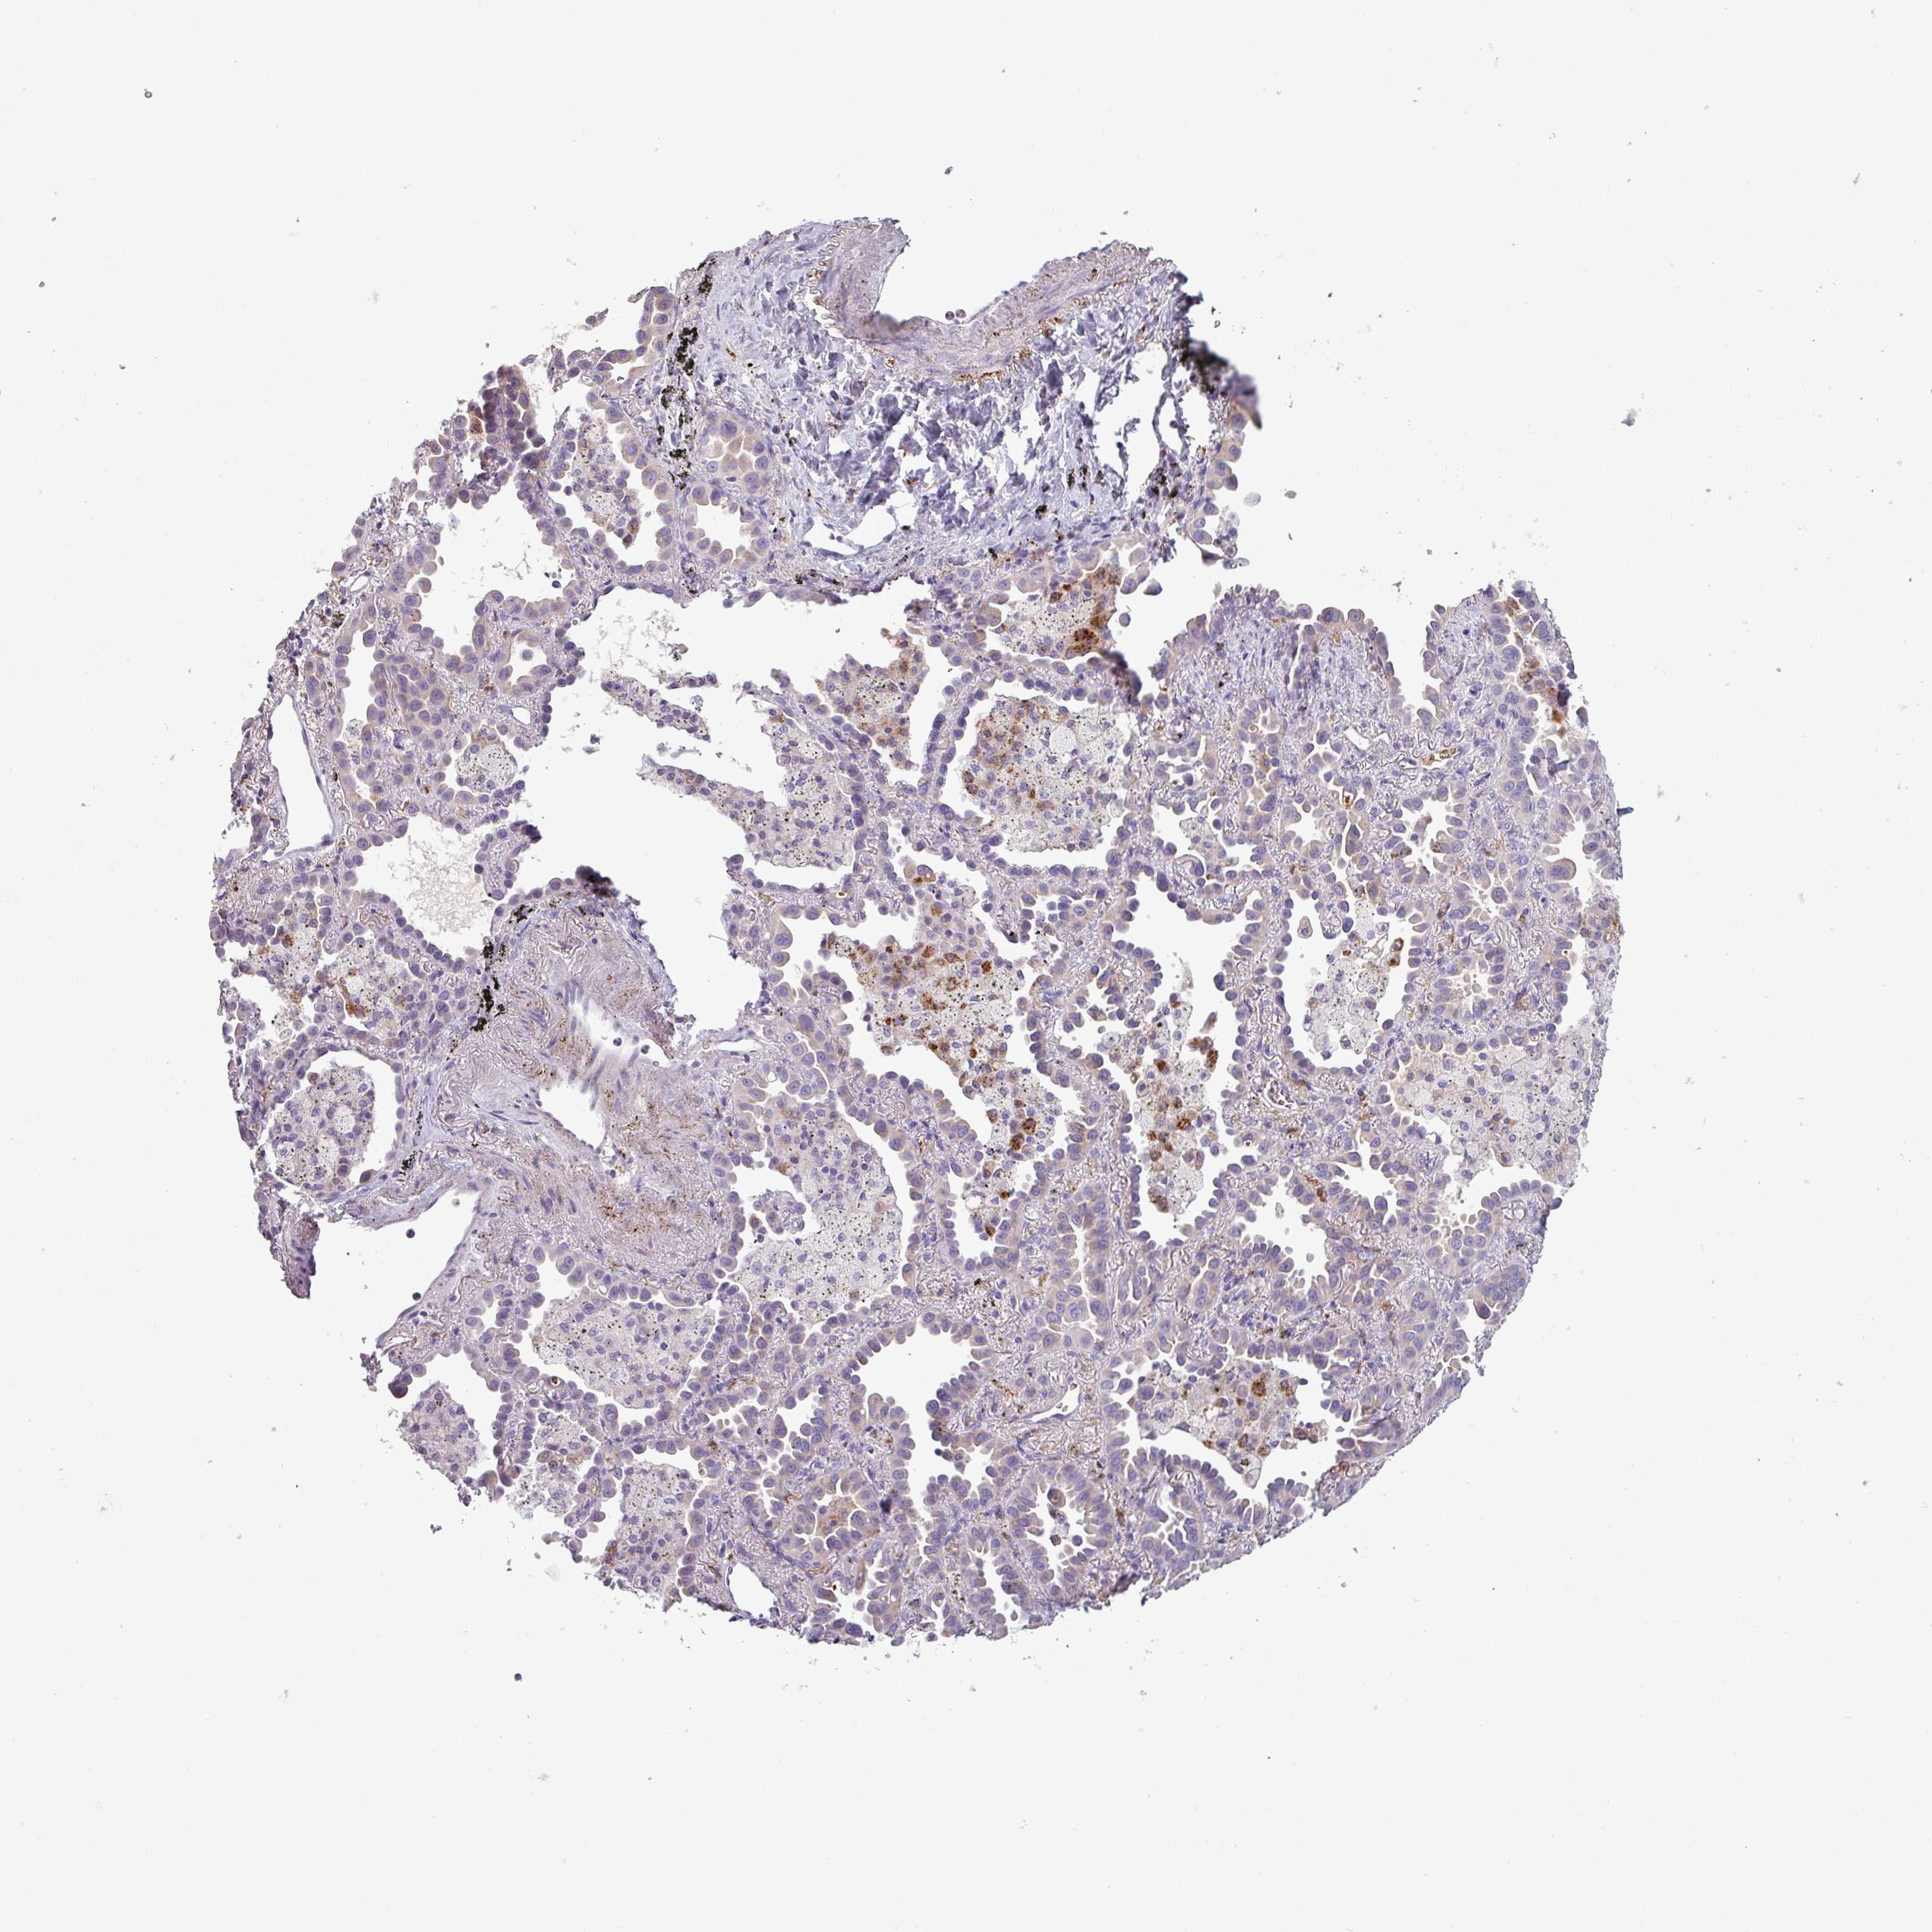

CANCER LUNG CANCER Show tissue menu

Lung cancer

Human cancer

Lung adenocarcinoma